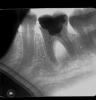

lyublyu85 Опубликовано 27 мая, 2012 Поделиться Опубликовано 27 мая, 2012 Здравствуйте!Очень хочется вылечить нижний 6-й зуб. Он мертвый, был залечен в августе 2011 г. Зимой образовалась дырка рядом с десной, около соседнего меньшего зуба (5-го наверно). 20 мая 2012 г. на внутренней стороне десны образовалась шишка (свищевой ход). Хирург отправил на рентген, посмотрел и сказал, что у меня самый наихудший случай - киста между корнями зуба, сказал полоскать содой и направил меня к парадонтологу. Она, в свою очередь, сказала, что ничего страшного тут нет, ходи пока не болит, а когда щека раздуется, приходи на удаление. Я от нее вышла в шоке.Дома, конечно, прополоскала, шишка очень уменьшилась, языком не чувствуется. Зуб, десна не болит, только "тукала" после осмотра хирургом. Еще в добавок я разболелась (насморк, кашель, боль в горле), что снизило мой иммунитет, поэтому сейчас, наверно, не стоит браться за зуб? только после выздоровления или я заблуждаюсь?Снимок есть только в отсканированном виде, поэтому цвета там, как на негативе: пломба черного цвета, киста белого. На снимке все наоборот, но думаю, Вы разберетесь что к чему. Кстати, вчера посмотрела на зуб сбоку, он темнее, чем соседние зубы (сероватого цвета). Надеюсь на вашу помощь в качестве профессиональной консультации по вопросам:1. Можно ли спасти зуб?2. Если да, то каким образом можно убрать кисту из-под зуба. Ссылка на комментарий

ger_berra Опубликовано 28 мая, 2012 Поделиться Опубликовано 28 мая, 2012 (изменено) Надо снимать пломбу и смотреть,что осталось от зуба.Даже если на дне перфорация(дырка),то можно попоробовать спасти.Если трещина ,то нет.Снимок малоинформативный. Изменено 28 мая, 2012 пользователем ger_berra Ссылка на комментарий